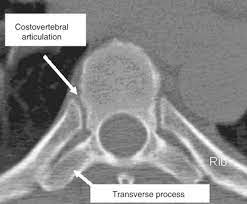

The transverse foramen is an opening on each of the transverse processes of the cervical spine which gives passage to the vertebral artery and vein and a sympathetic nerve plexus. There are two transverse processes that extend off each vertebra in the details: Transverse process fractures are common sequelae of trauma, although they are considered a minor and stable lumbar spine fracture. Transverse processes are typically fractured in direct blows from athletics touch or impact from falls from bikes/motorbikes or by heights. However, postmortem computed tomography (pmct) has made detection of this type of injury easy. There are two transverse processes that extend off each vertebra in the spine, one on each side. A transverse process fracture is a break in 1 or more transverse process. In 78% of transverse process fractures, ct scanning showed that the fracture extended into the transverse foramen. A transverse process fracture is considered as a rare injury. A transverse process fracture is a break in 1 or more transverse process. What is a transverse process fracture? Transverse process fractures caused by stress are likely under detected since even an acute transverse process fracture requires a high index of suspicion to be correctly identified(4,7). If ct confirms isolated injury lateral flexion/extension views are indicated to rule out dynamic instability.

However, postmortem computed tomography (pmct) has made detection of this type of injury easy. There are two transverse processes that extend off each vertebra in the details: What is a transverse process fracture? It may occur as an avulsion fracture due to strong contracture of the muscles. It occurs as a result of sudden and extreme trauma. If ct confirms isolated injury lateral flexion/extension views are indicated to rule out dynamic instability. Vertebral angiography, performed in eight patients with fractures involving the transverse foramen, showed dissection or occlusion of the vertebral artery in seven (88%) instances. This part extends out from the side of the main body of the bone (called the vertebral body). A transverse process fracture at the level of l5 is a surrogate marker of vertical instability of the pelvic fracture due to the attachment of the iliolumbar ligaments. We retrospectively reviewed the reports of lumbar spine and abdominopelvic ct scans from 2017 and 2018 to classify the types of spine fractures, their mechanism of injury, treatment and. Up to 60% of lumbar transverse process fractures identified on ct will be missed on plain radiographs. In 78% of transverse process fractures, ct scanning showed that the fracture extended into the transverse foramen. Transverse process fractures identified on helical computed tomography (ct) scans without the presence of any other fracture or.